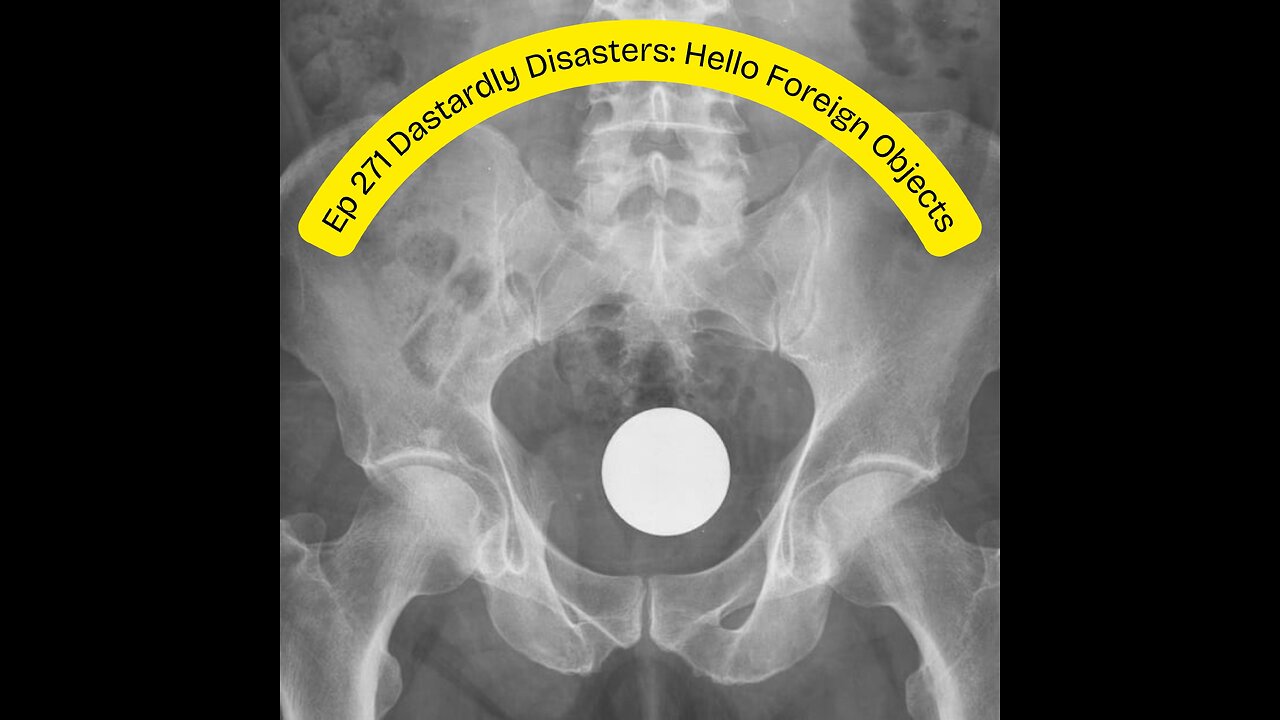

Deplorable Nation Ep 271 Dastardly Disasters: Hello Foreign Objects

Joined by Heidi (Unfiltered Rise) for a discussion on foreign objects in the body. Whether intentional or accidental, foreign body retrieval or surgical removal is essential. Objects tend to get lodged not just at the point of impact or insertion, but they can also travel, penetrating vital organs and causing body-wide infections. Join us on this hilarious episode of play stupid games/win stupid prizes.